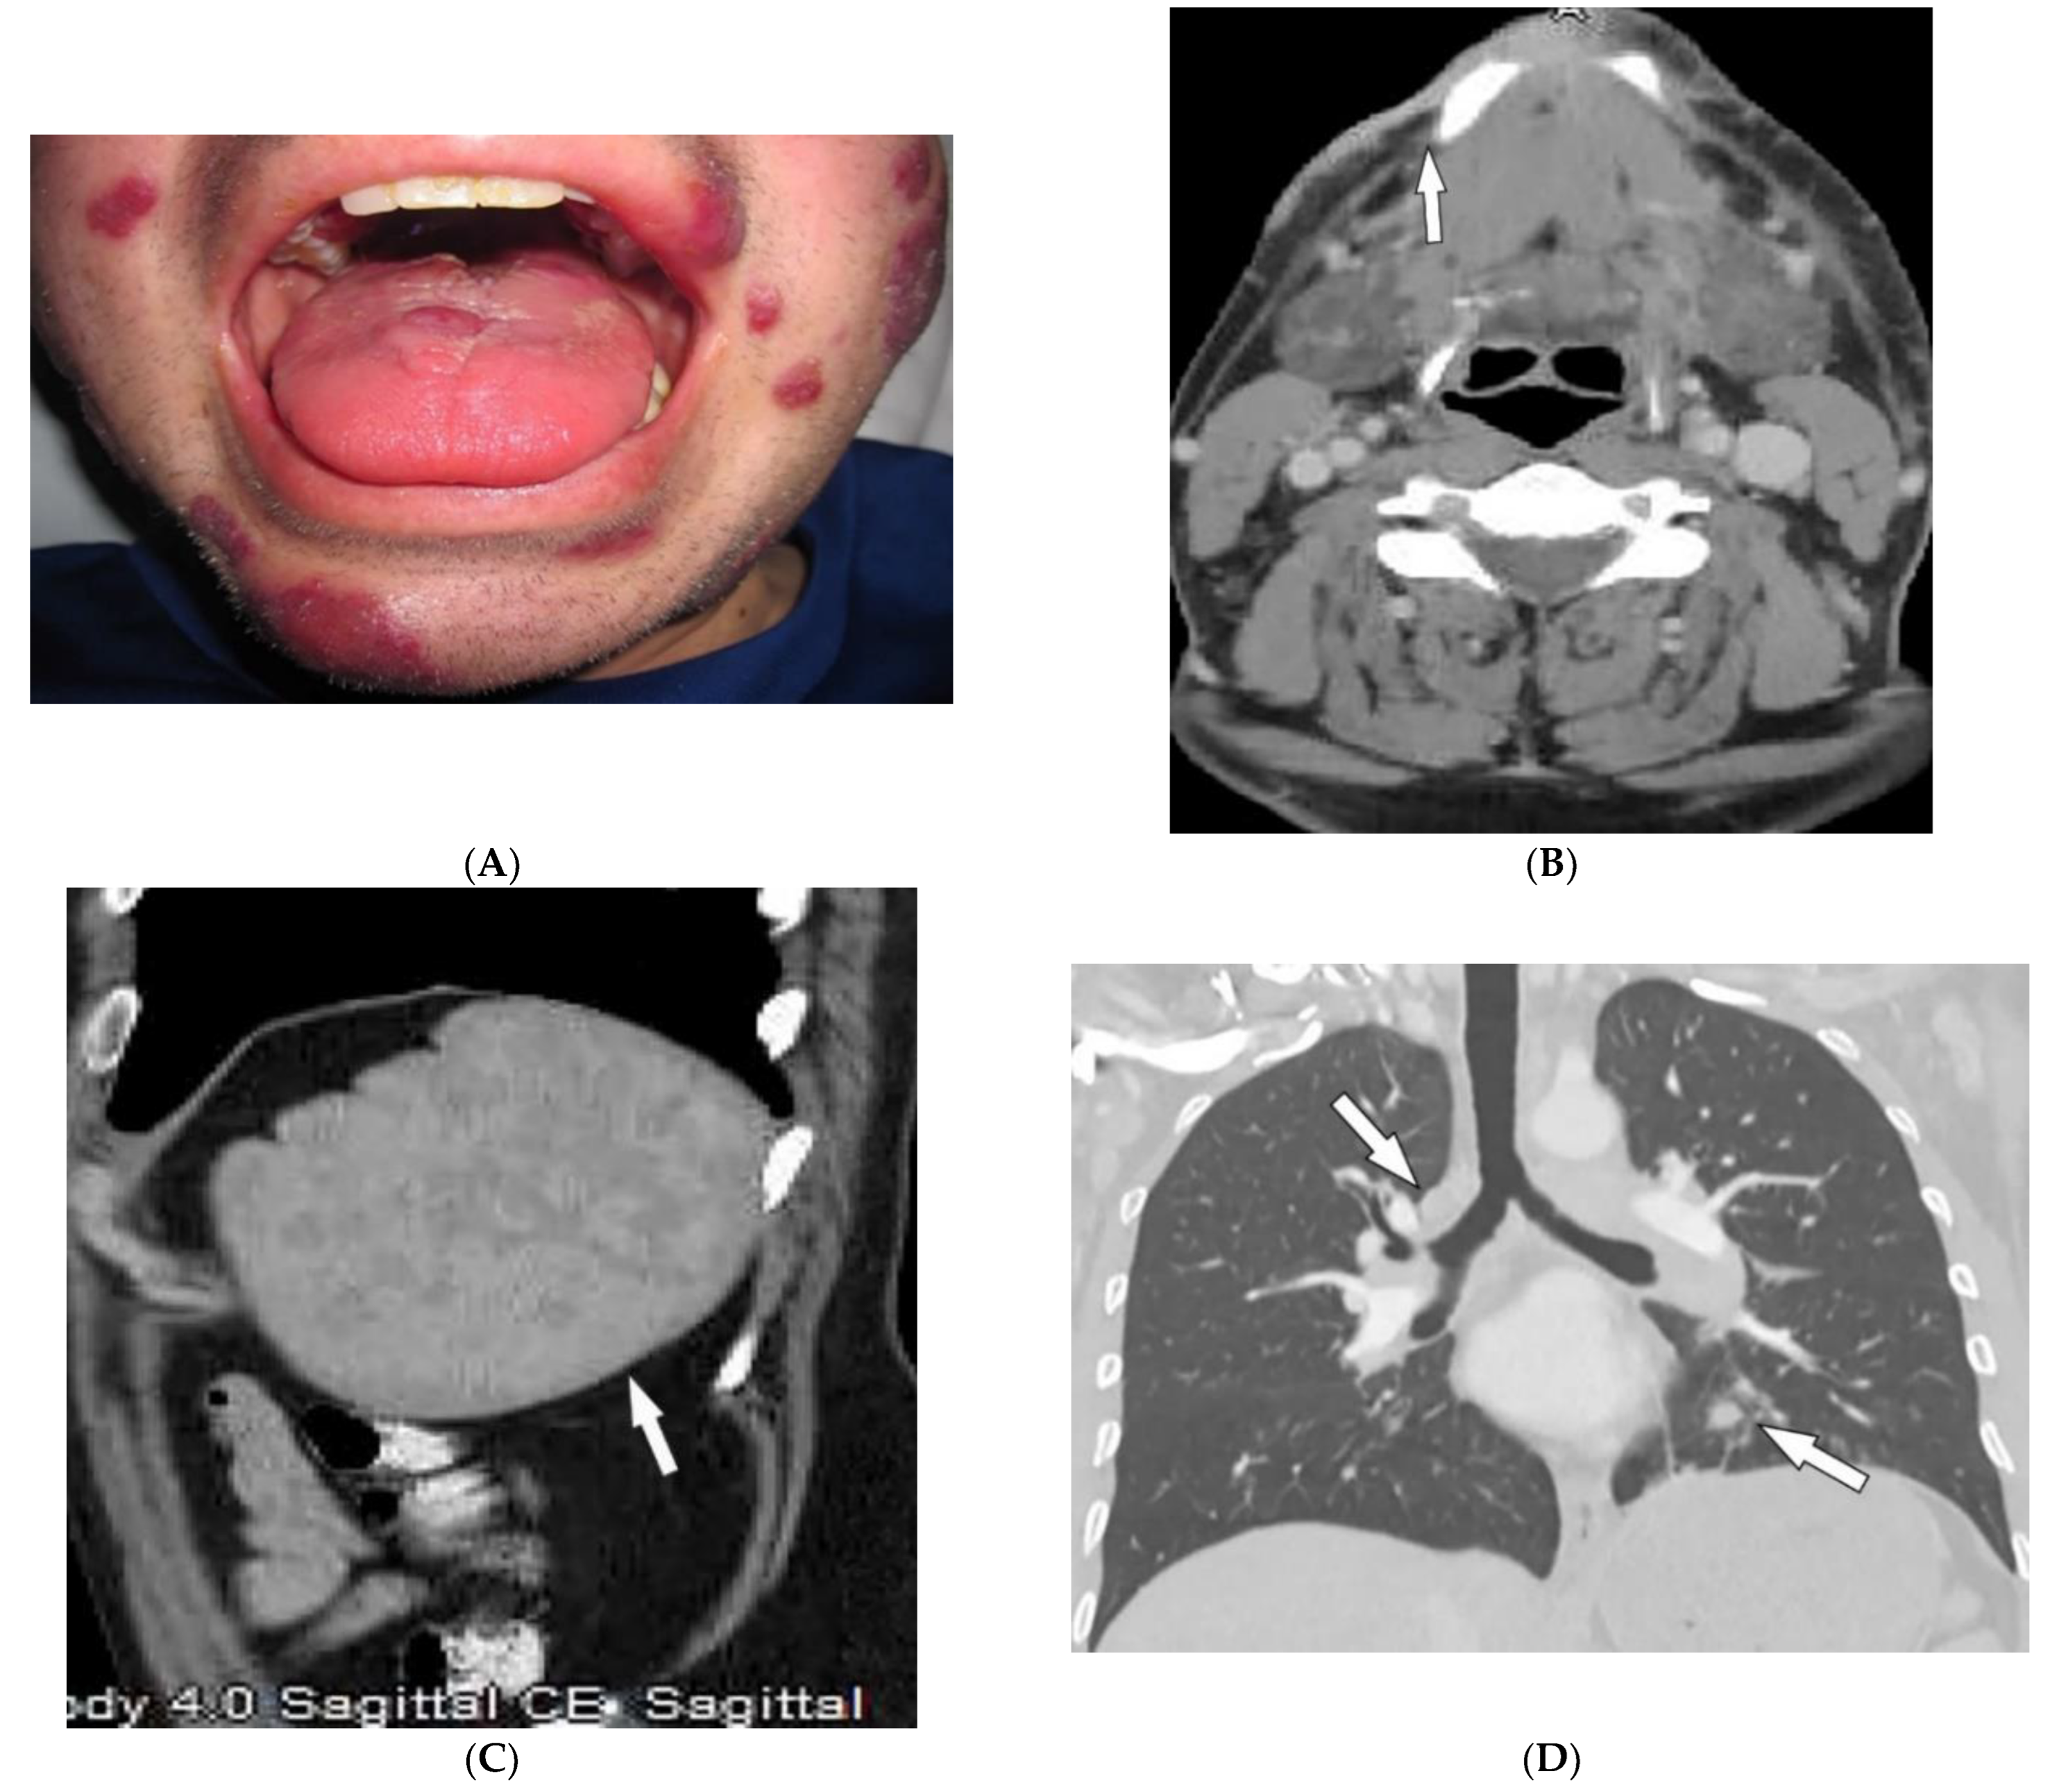

4.2. Kaposi Sarcoma

| Kaposi sarcoma | Erythematous or violaceous macules, plaques, nodules Pulmonary involvement Gastrointestinal involvement | Nodular enhancing masses Peribroncovascular nodules and halo sign |